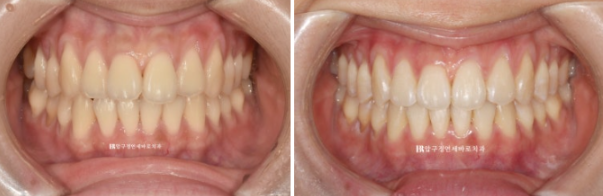

치료 전 - 치료 후 비교 사진입니다.

초진 24.02 이며 치료 종료는 24.07입니다.

24.02~24.07

소량의 치간삭제로 블랙트라이앵글 없이 치료를 마무리 했습니다.

좋은 교합은 유지가 되었고

토끼이빨은 정상 배열을 찾앗습니다.

깔끔해진 미소를 가지게 되었습니다.